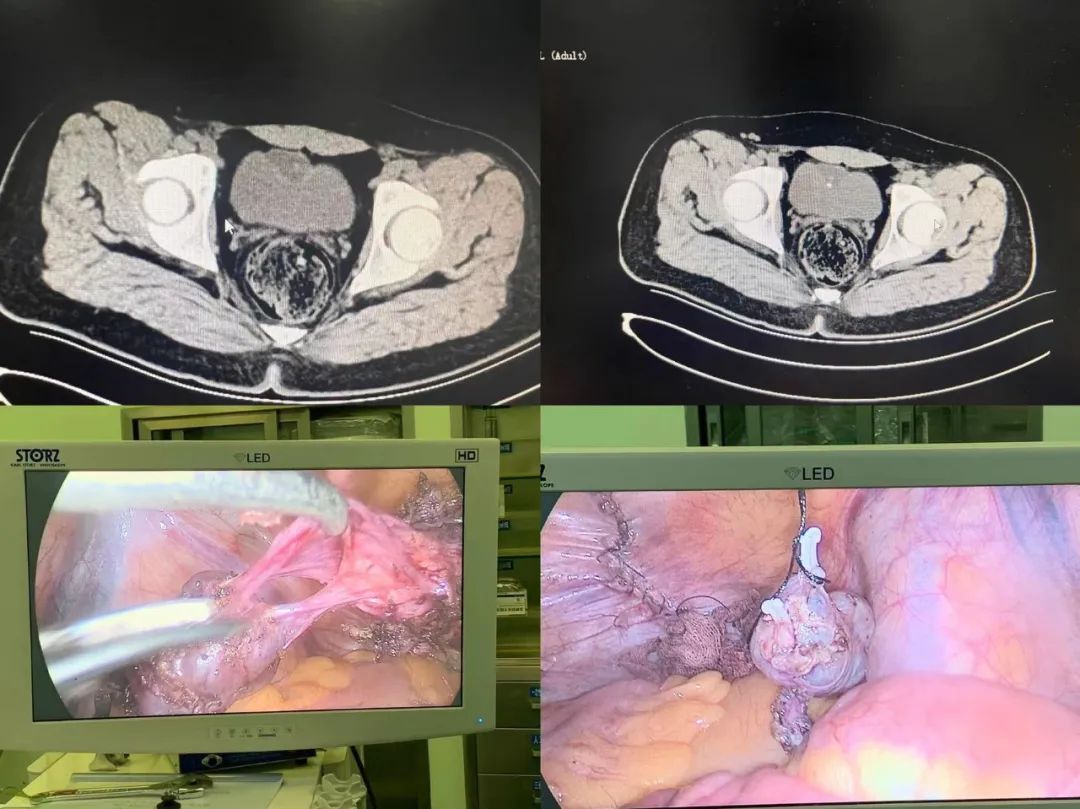

近日,我院小儿外科为一位脐尿管囊肿患儿成功实施“腹腔镜下脐尿管囊肿切除术”。此次手术为通辽市首例腹腔镜下完整切除脐尿管囊肿,术中结合术中超声,更有效地定位囊肿与膀胱的边界,大大提高手术安全性,最大限度地减少了对患儿的损伤,术后三天患儿康复出院。

脐尿管为膀胱顶部向脐部延伸的管状结构,是尿囊胚内体腔部分的退化残余,一般出生前及婴儿期管状结构退化成无功能的纤维条索,称为脐中韧带。脐尿管囊肿是脐尿管两端闭合而中间段管腔未闭,内由管壁上皮层的分泌液填充呈囊性扩张,其主要治疗方式为手术治疗。“腹腔镜下脐尿管囊肿切除术”效果及彻底性等同开腹手术,具有损伤小、术后恢复快、伤口美观等特点,手术的成功标志我院在儿童腹腔镜水平又上新台阶。